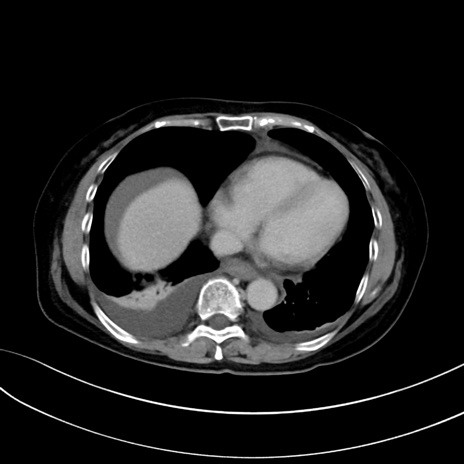

(冠状断像)1日半後